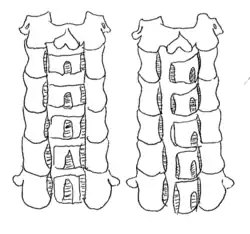

Open door laminoplasty

The C2 to C7 laminae are drilled at the lateral borders of the laminae. One side of the bone is completely cut, while the other side acts as a hinge. The laminae are then lifted to increase space in the spinal canal. The flap of the laminae is kept open with a suture that is fixed to the facet capsule.[1][5]